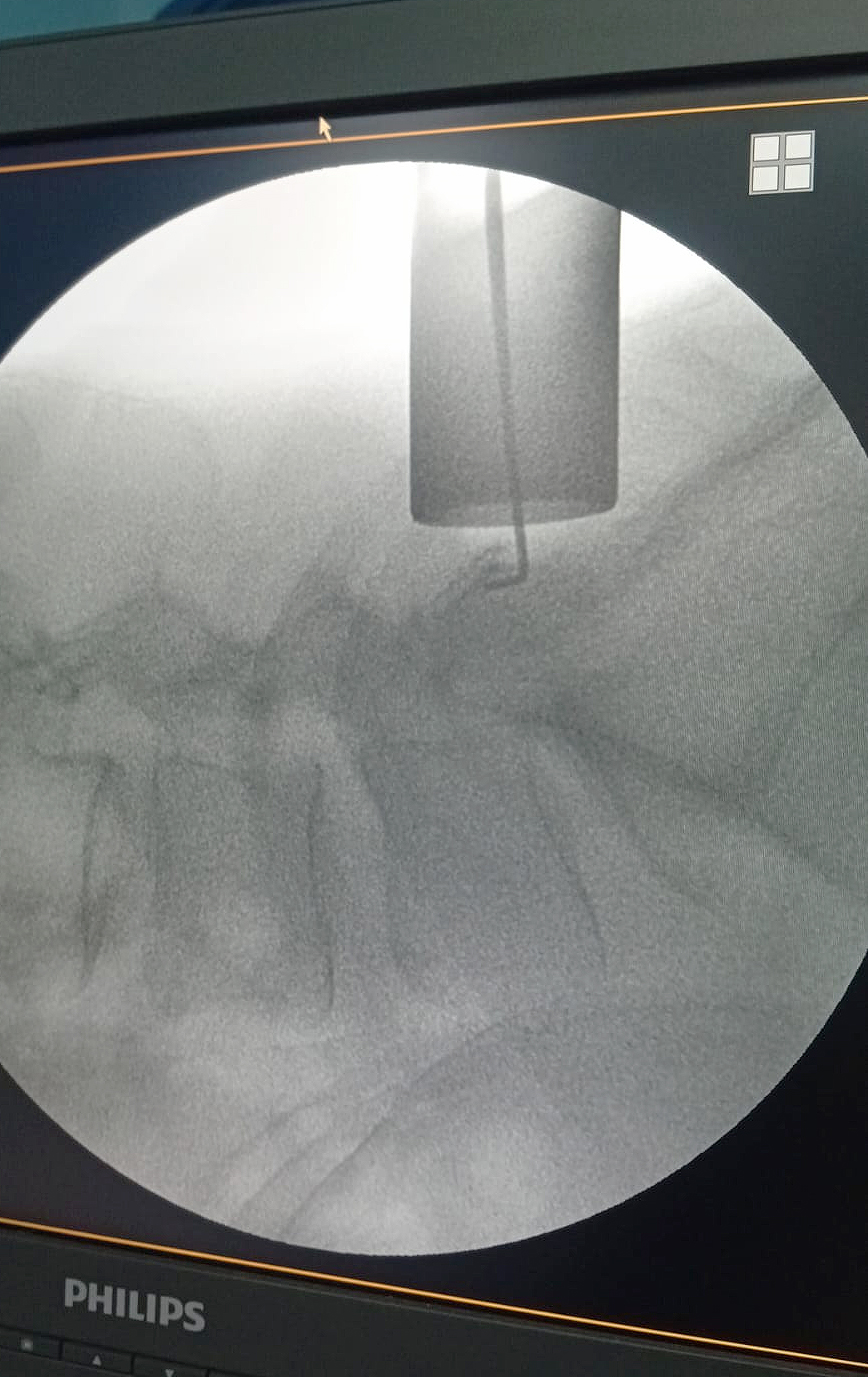

Una resonancia magnética de columna lumbar evidenció la presencia de un quiste facetario sinovial a nivel L5-S1 derecho, el cual comprimía la raíz nerviosa L5, generando los síntomas incapacitantes.

Ante este diagnóstico, se procedió a una cirugía de exéresis del quiste y liberación radicular mediante un abordaje tubular mínimamente invasivo. El procedimiento fue liderado por el neurocirujano Dr. Néstor Romero, quien explicó que la intervención fue un éxito: